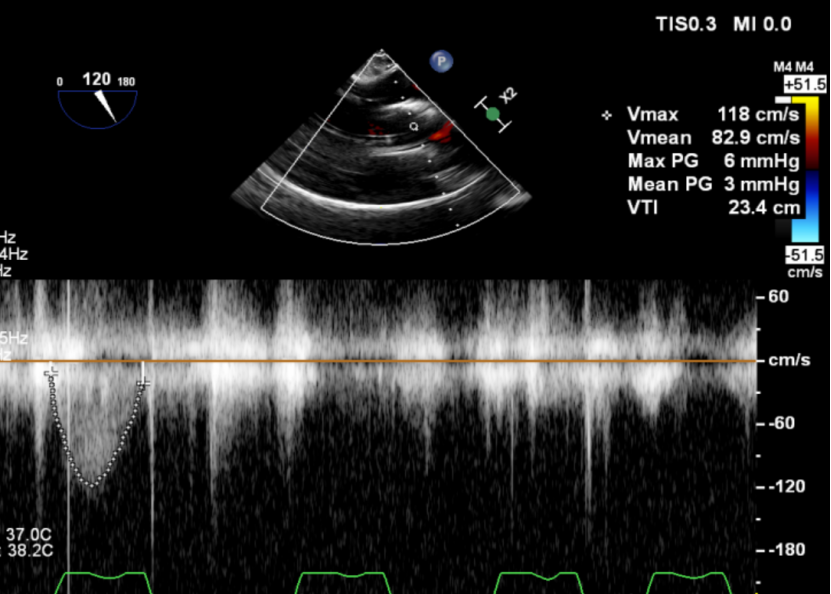

脱钩后输送器回收,瓣膜无位移及形变,确认瓣膜完全脱钩,回撤输送系统,超声再次评估,瓣膜位置及形态良好,无瓣周漏,峰值流速1.18m/s,平均压3mmHg,患者未诉不适,入路缝合后返回病房。